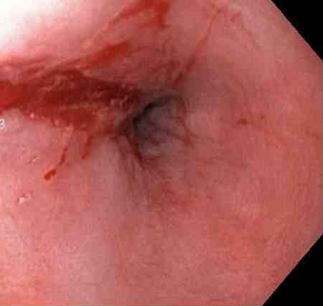

A mechanical method (e.g., clips) with or without adrenaline (epinephrine). In practice, both through-the-scope clips (TTSC) and over-the-scope clips are options depending on availability and expertise. However, for MWT, TTSC usually suffice.[Figure caption and citation for the preceding image starts]: Mallory Weiss tear after application of through-the-scope clip results in haemostasisFrom the personal collection of Douglas Adler; used with permission [Citation ends].

TTSC use is as safe and effective as other methods for controlling actively bleeding lesions.[76][77][78][Figure caption and citation for the preceding image starts]: Mallory Weiss tear after application of through-the-scope clip results in haemostasisFrom the personal collection of Douglas Adler; used with permission [Citation ends].

Actively bleeding lesions. [Figure caption and citation for the preceding image starts]: Bleeding Mallory Weiss Tear viewed on retroflexionFrom the personal collection of Douglas Adler; used with permission [Citation ends].